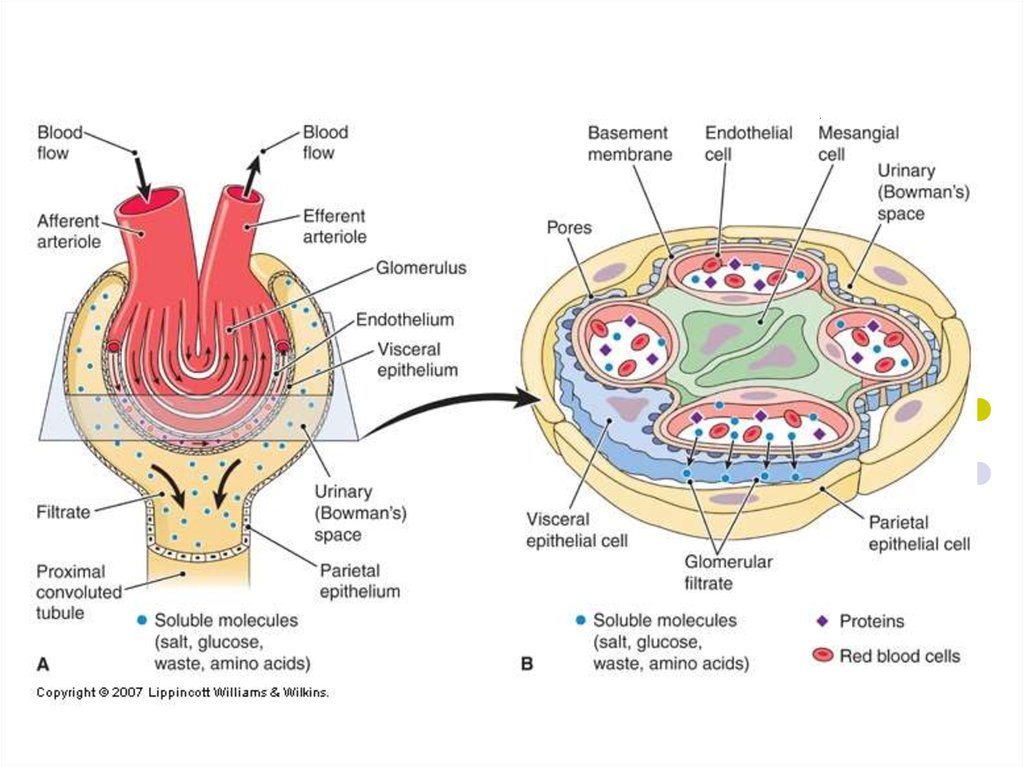

Механизм остро го диффузного гломерулонефрита